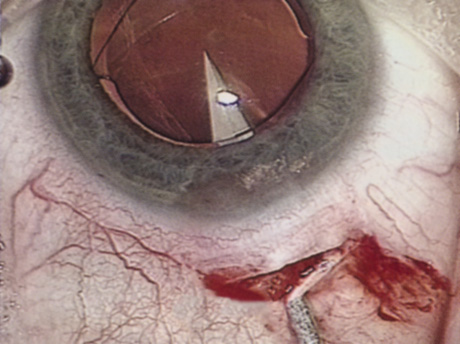

PARABULBAR ANESTHESIA

Various approaches can instill anesthetic into the subconjunctival or subtenon space using either a needle or a posteriorly directed blunt cannula.70 Parabulbar anesthetics are fairly effective for anesthesia, although they generally achieve less than maximal akinesia. Ballooning of the conjunctiva may cause fluid to build up around the limbus, creating a fluid meniscus lens, markedly limiting surgical visualization (Fig. 8). A posteriorly directed cannula in the parabulbar space could disturb a vortex vein. These injections also may induce unsightly subconjunctival hemorrhage. The authors reserve parabulbar anesthetic techniques primarily for augmentation of anesthesia when an initial anesthetic has either worn off or proved ineffective.

Fig. 8. Chemosis can cause pooling of the irrigation fluid, which creates a negative meniscus lens, inhibits the view, and reduces stereopsis.